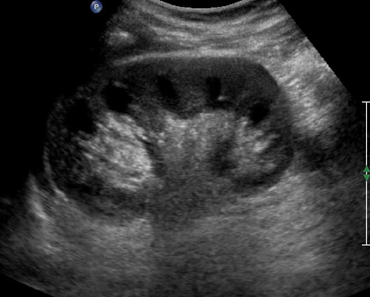

Проверка органов брюшной полости бывает комплексной, изучают и отдельные органы. В проверку входит исследование печени на:

- Гепатит, гепатоз.

- Трансформации, цирроз.

- Новообразования.

Просматривается желчный пузырь, визуализируются желчные протоки, изучаются на предмет аномалий, отклонений. Комплексное исследование диагностирует опухоли органа, воспаления, камни, полипы.

Изучается селезёнка, метод выявляет травмы, воспаления. Обнаруживаются аномалии формирования, смещения, инфаркт. Отмечаются модификации при проблемах кровеносной системы, абсцессы. Исследуется поджелудочная железа, расшифровка демонстрирует воспаления, кисты, нарушения строения. Не знающим, какие органы проверяют, отвечаем, что исследование включает сосуды, УЗИ распознает тромбоз.